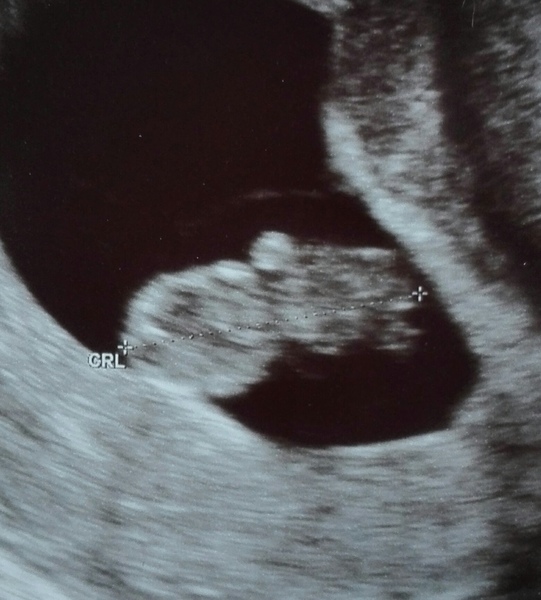

Een vroege echo rond 7-8 weken zwangerschap, kijkt de echoscopist of het bevruchte eitje zich op de juiste plek in de baarmoeder heeft ingenesteld (niet buitenbaarmoederlijk) en of het hartje klopt Het moment vanaf de positieve zwangerschapstest waarbij je zoveel weet: IK BEN ZWANGER, maar tegelijkertijd ook nog helemaal niets

Waarom een echo voor 8 weken juist onzekerheid kan geven! De meeste vrouwen hebben wij voor het eerst aan de telefoon bij een zwangerschapsduur van 4 tot 5 weken Hebben jullie bij de echo rond 8-9 weken een kloppend hartje gezien, dan is die kans al veel kleiner en eind nog maar 2 tot 3 van de 100 zwangerschappen in een miskraam . Hoe ziet foetus van 8 weken eruit? Na 8 weken spreken we van foetus omdat alle organen in beginsel aanwezig zijn.

Zwangerschapsupdate Week 8 de eerste echo! Moonoloog. De kans dat het nog mis gaat bij 8 weken is 0,5 %, terwijl iedereen begint met 20% Houd er ook rekening mee dat als je toch iets priller zwanger bent dan verwacht, het nog niet te zien is of het hartje.

2D Echo 8 Weken Zwanger YouTube. De echoscopist kijkt onder andere of er een levend vruchtje te zien is en of deze goed is ingenesteld Het begint met het resultaat van een meting en daarna volgt een live filmpje